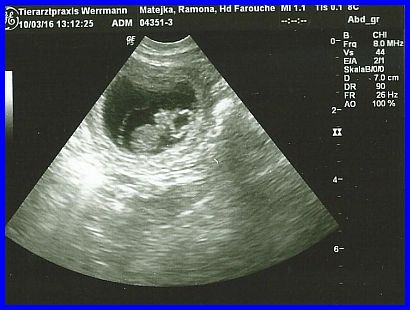

Im oberen Teil des Bildes ist die Fruchtblase als schwarzer Kreis zu erkennen, das graue Gebilde darin ist ein Welpe.

Auch hier wieder sehr gut zu erkennen, ein schon relativ großer Welpe. Die Welpen sind hier 29 Tage alt!